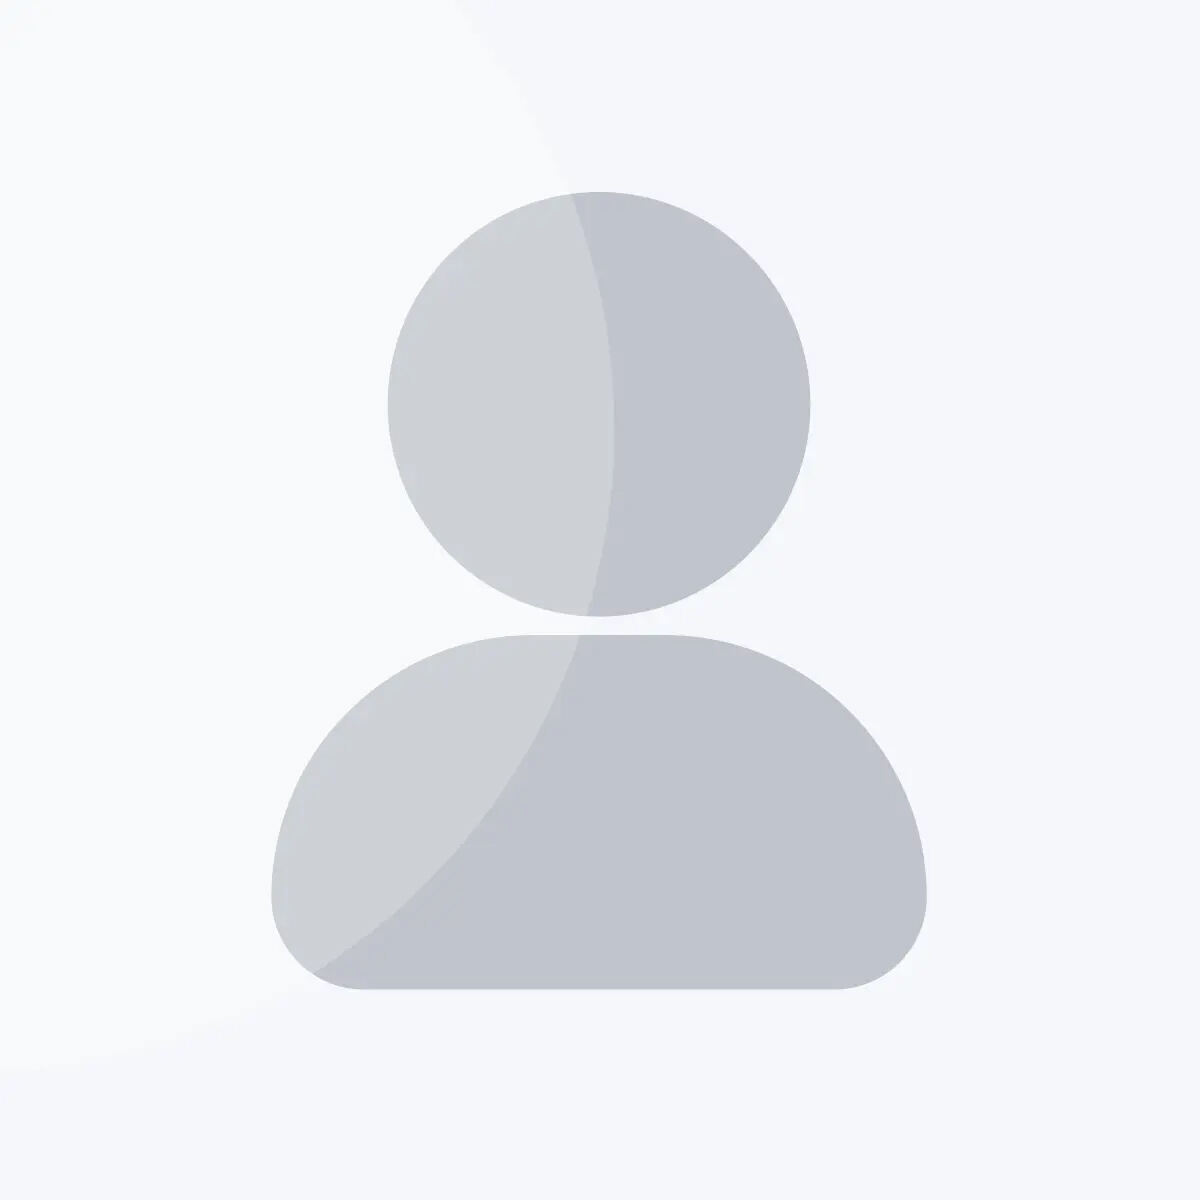

There are two patterns of ECG alteration in Wellens syndrome: type A and type B. Type A, which accounts for 25% of cases, is characterized by biphasic T waves with initial positivity and terminal negativity in leads V2 and V3. Type B, on the other hand, accounts for 75% of cases and is characterized by deeply and symmetrically inverted T waves in leads V2 and V3 (Fig. 1). Despite the differences in the ECG patterns, the progression from type A to type B pattern may occur as a consequence of ischemic damage progression, as proposed by S. W. Smith in his book “The ECG in acute MI” [1].

Fig. 1.

Fig. 1.Electrocardiographic (ECG) changes in Type A (left) and Type B (right) Wellens syndrome.